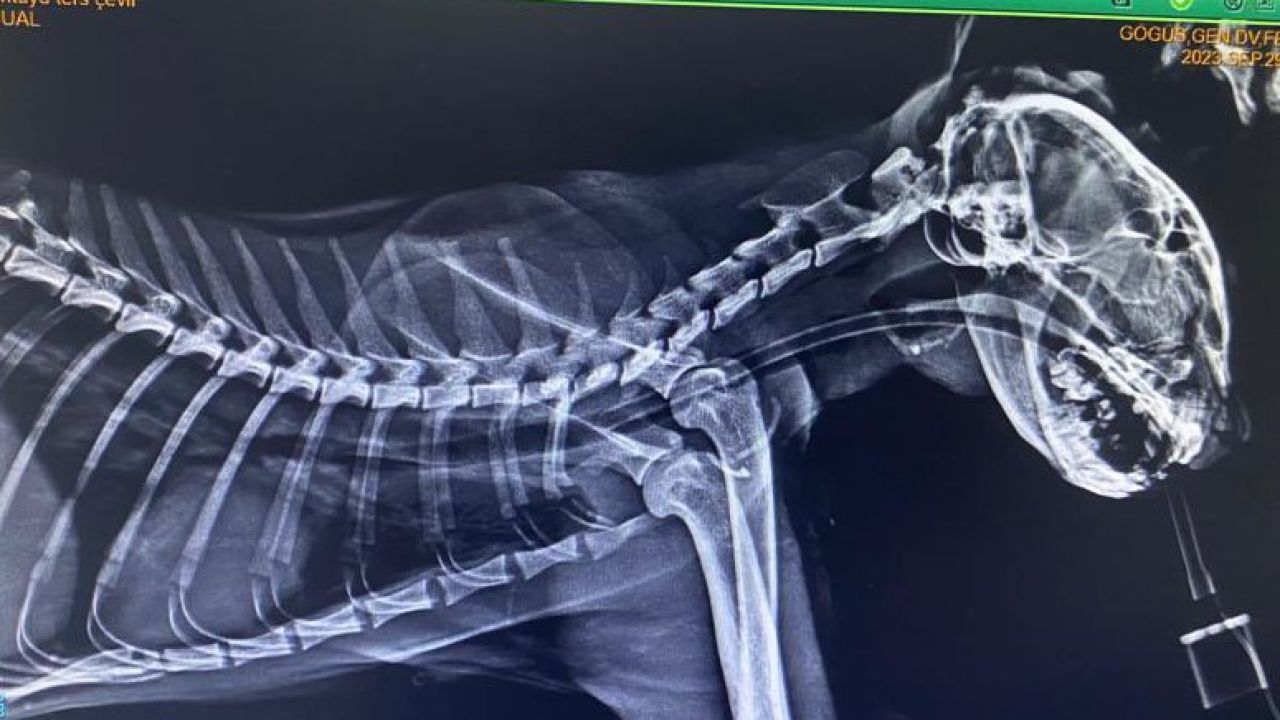

Zonguldak’ta bir sokak kedisinin boğazından üç olta kancası çıktı. Ameliyata alınan kedinin boğazındaki kancaların derine saplandığı ortaya çıkarken ameliyatın ardından sağlığına kavuştu.

Kilimli ilçesinde bir sokak kedisinin ağzında kanca olduğunu gören vatandaşlar durumu hayvansever Seda Mercan’a iletti. Kediyi bulan Mercan, zabıta ekiplerinden yardım istedi. Veteriner hekime getirilen sokak kedisinin röntgeninde boğazına saplanmış üç tane olta kancası olduğu tespit edildi. Ameliyata alınan kedinin boğazındaki kancalar çıkartıldı. Yaklaşık bir saat süren ameliyatta kancaların derine saplandığı görüldü. Ameliyattan sonra kedi sağlığına kavuşurken veteriner hekim Furkan Alkan, süreci şöyle aktardı:

"Vaka geldiği zaman ağzında salya akıntısı ile geldi. Üç günden beri bu haldeymiş. İlk yaptığımız muayenede kancanın bir kısmını gördük ve hemen röntgeni çektik. Röntgende 3 tane kancanın boğazına takıldığını gördük. Endoskopi yardımıyla 3’ünü birden çıkardık. Üçü de çok derine saplanmıştı. Yarım saat bir saatlik bir operasyonla arkadaş sağlığına kavuştu. Ya balık alırken ya da balıkçılar tarafından atılan balığı kaparken kancayla beraber kaptı. Kancaları yuttu. Oraya saplandığı için de ne ağızda kaldı ne de mideye gitti. 3-4 günden beri enfeksiyonlu ağız akıntısı varmış, kliniğimize gelip tedavisini gördü. 4-5 yaşlarında sokak hayvanı. Bir hayvansever tarafından getirildi. Masraflarını hayvansever karşılıyor."